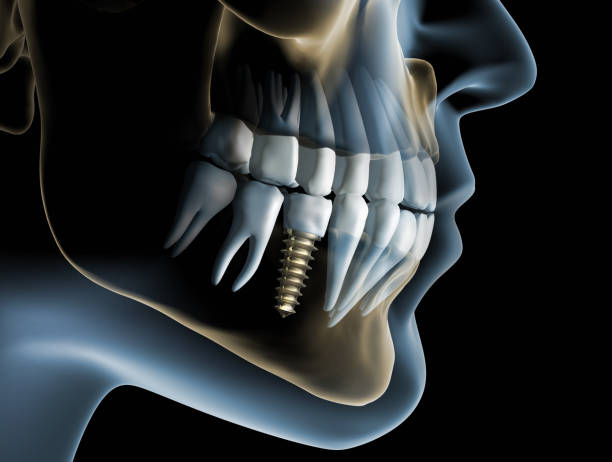

Implant to tytanowy element o niewielkim rozmiarze, który zastępuje naturalny korzeń zęba. Dzięki niemu możemy posadowić w miejscu braku koronę, oprzeć most bądź wesprzeć protezę. To bezpieczne rozwiązanie, dające szereg możliwości.

Współczesna implantologia daje szeroki wachlarz rozwiązań, a przy tym pozostaje najbardziej bezpieczną, przewidywalną dziedziną, która pozwala na uzupełnienie pojedynczych lub pełnołukowych braków zębowych.